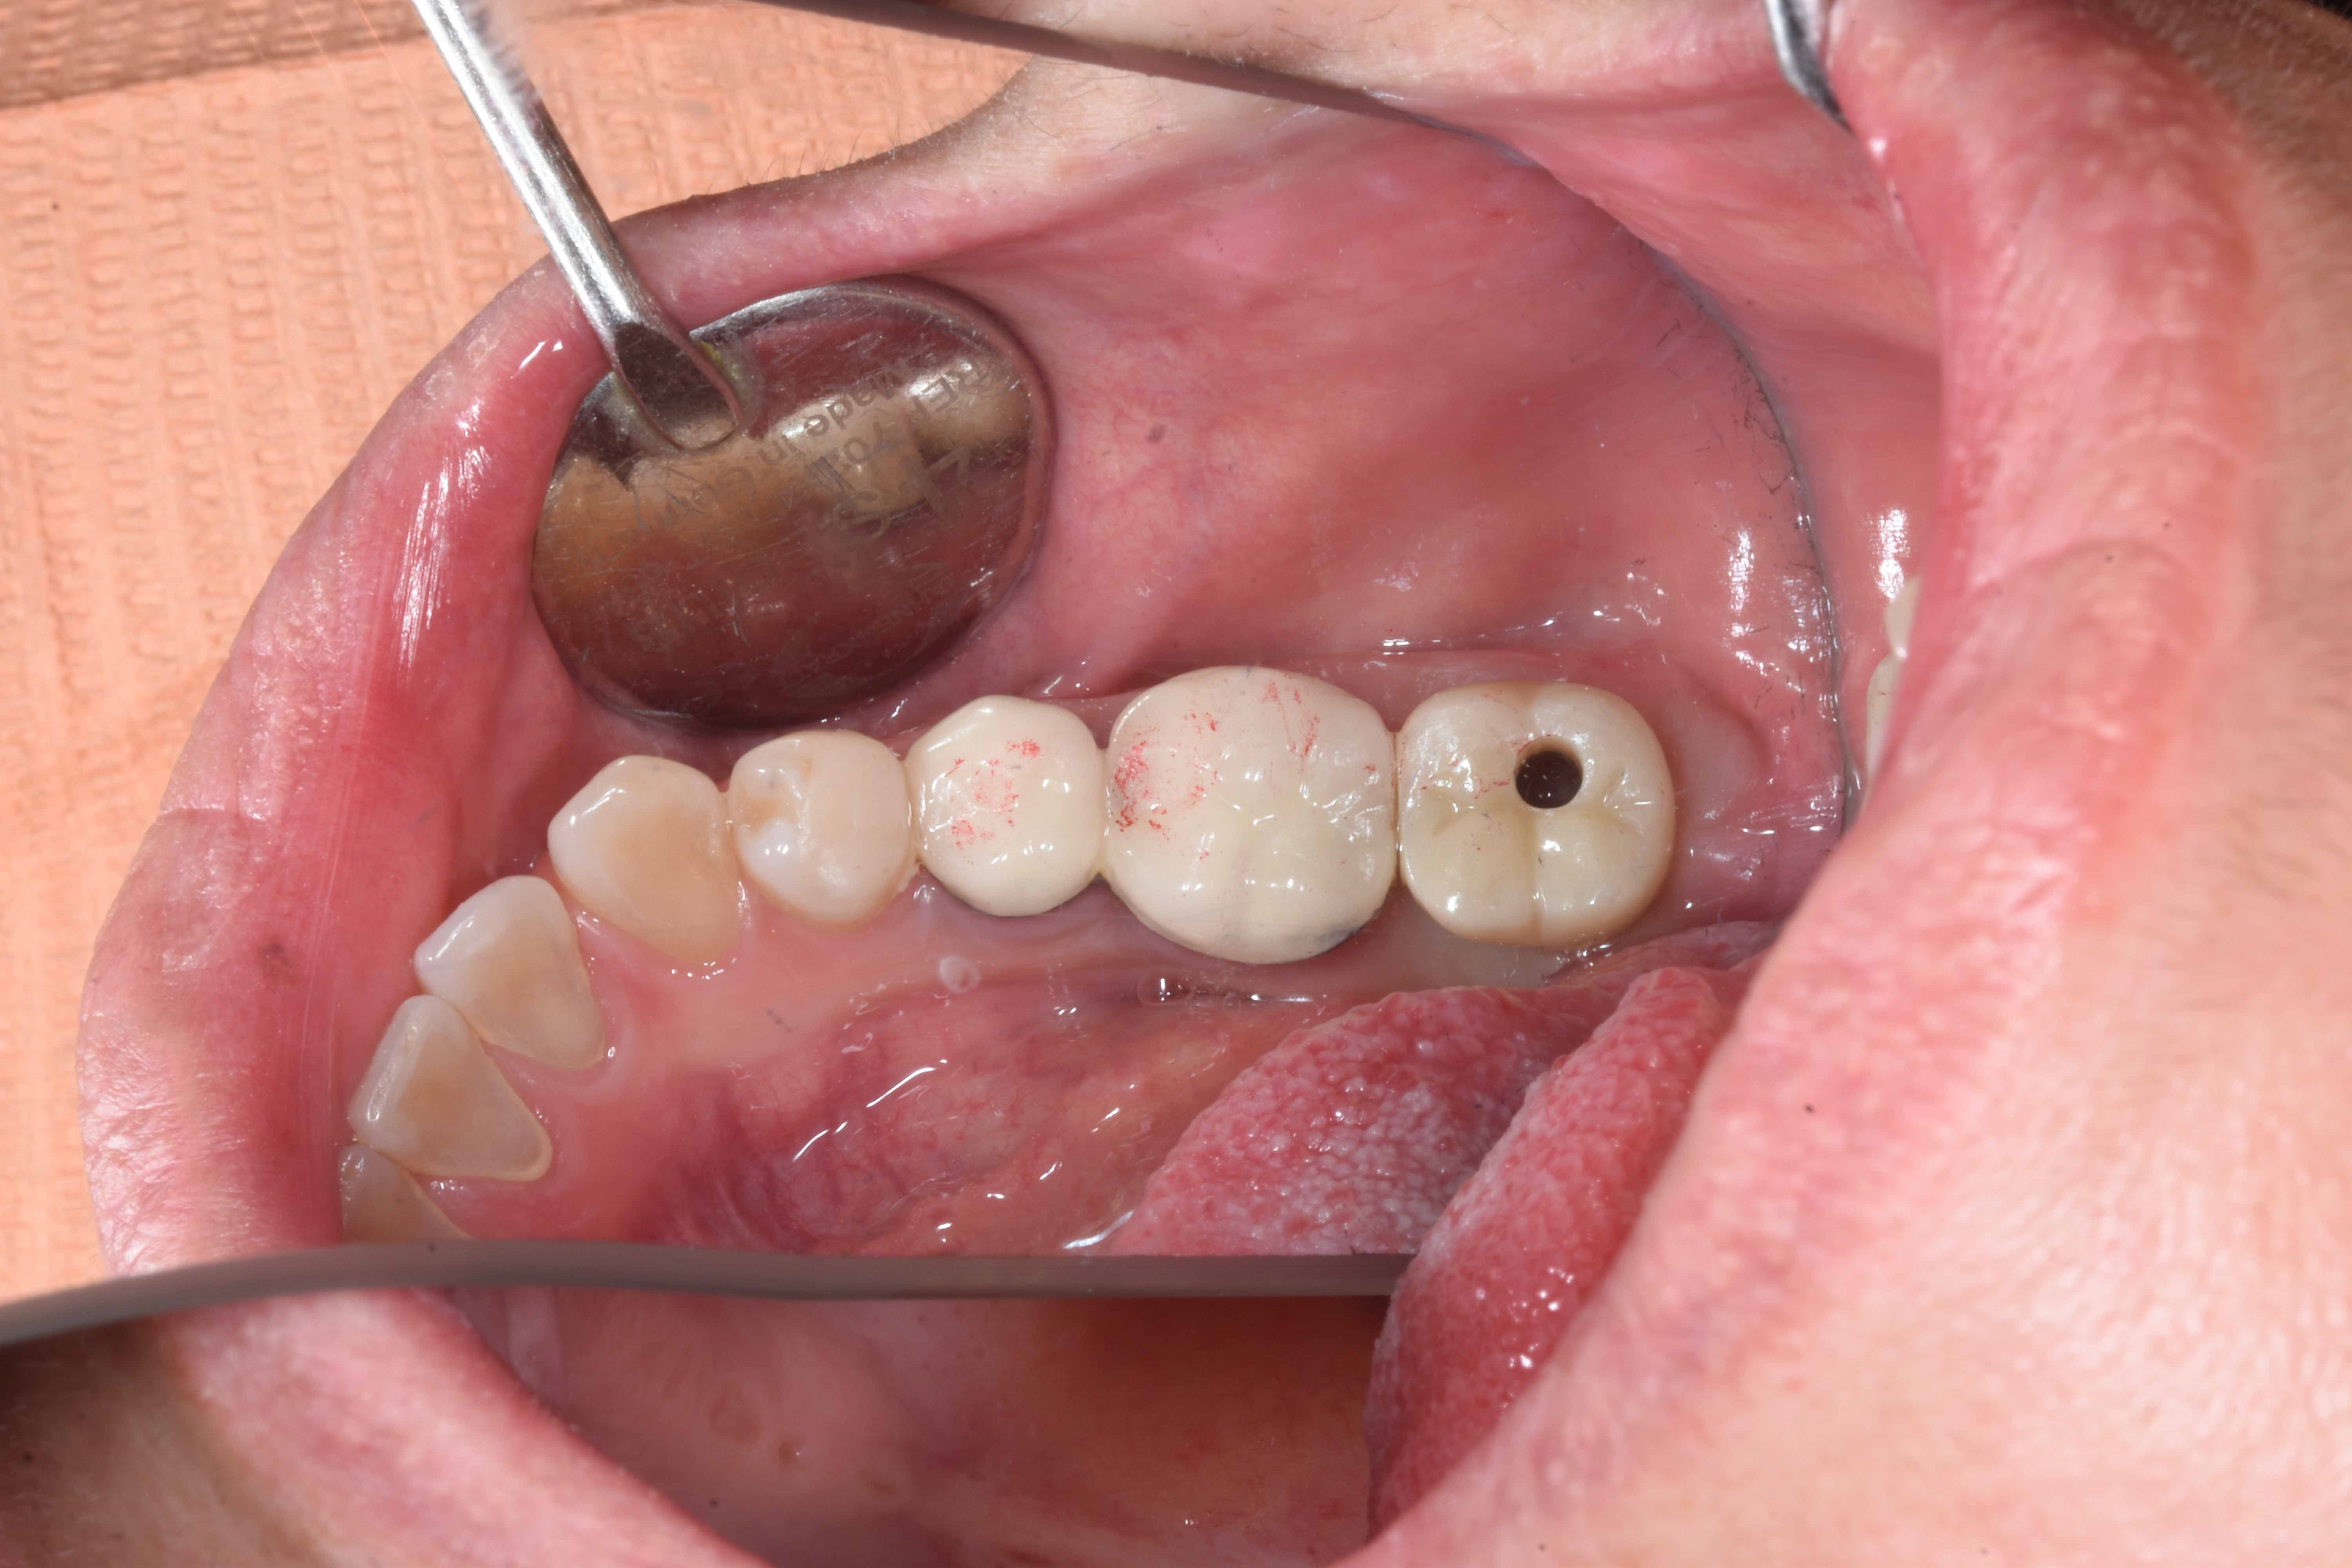

案例二

立即拔除壞牙根

當天完成植牙手術,並鎖上癒合螺帽

2-3月癒合,取下癒合螺帽,透過數位口掃至技公所製作假牙

7-10天完成假牙,試戴、調整咬合高度並鎖上,封填,完成